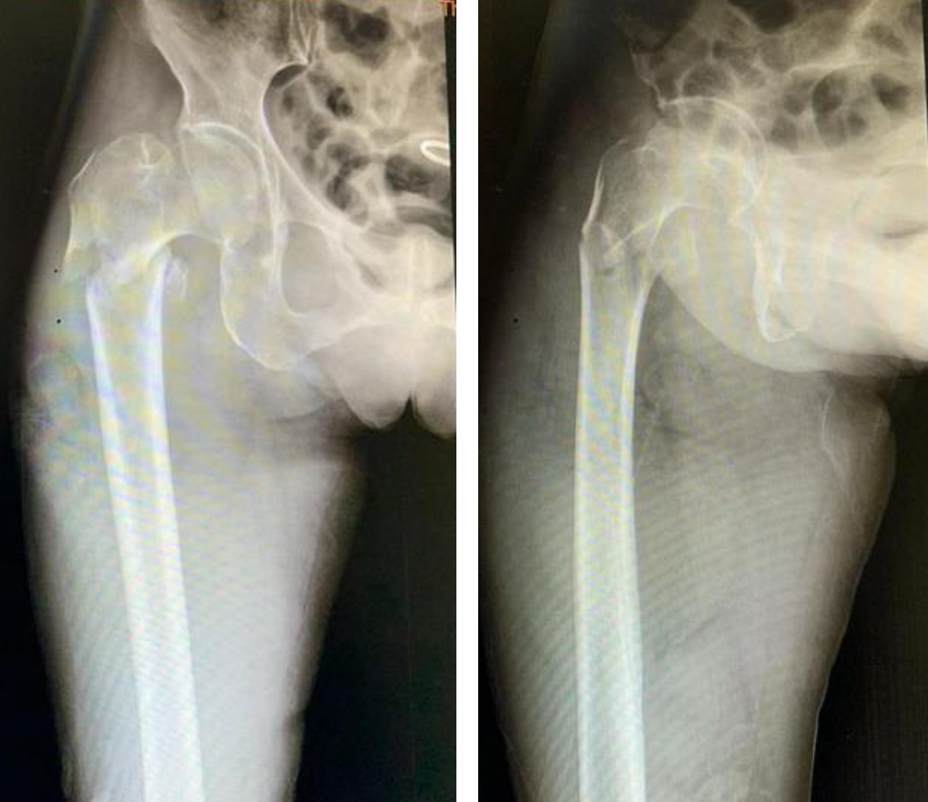

医院创伤骨科主任、老年髋部骨折多学科合作(Multiple Disciplinary Team,MDT)负责人罗令介绍到:“老人为右股骨转子下骨折,也被称为‘人生最后一次骨折’,非手术治疗极可能由于各种并发症危及患者生命,国际指南要求在伤后48小时内完成手术,尽快恢复行走,但手术治疗确实对于高龄老人而言风险极大,并且老人体质极弱(体重30kg),合并有肺部炎症、高血压病、陈旧性肺结核等基础疾病,稍有不慎,恐怕后果严重。MDT恰好能发挥医院多学科快速会诊的优势,以最快速度重建老人的骨骼,尽可能减少并发症,从而恢复健康”。罗令教授、郭强博士团队随即启动MDT,为老人早期手术开辟绿色通道。骨科、麻醉科、血管外科、心内科、呼吸内科等相关科室仔细研究老人病情,给老人制定了可行的手术麻醉方案和应急预案,为术后并发症的预防及康复治疗制定了合理周密的计划。

入院不到24小时,术前准备已完善。在麻醉科的协同努力下,罗令教授团队为患者行右股骨转子下骨折闭合复位+髓内钉(PFNA)固定术,手术仅用时15分钟,骨折复位且固定可靠,出血量不足50ml,手术切口不足5cm。为争分夺秒节约台上的每一分钟,医生们一直在射线下操作,当手术完成的那一刻,罗令教授脱下30斤重的铅衣,他的整个后背已被汗水浸透。微创手术、先进的“鸡尾酒”式镇痛等多模式疼痛管理,以及术后护理康复的积极介入,MDT理念渗透到了此次治疗的每一个环节。术后第二天老人便恢复了站立并缓慢行走,良好的康复获得了患者及家属的连连称赞。家属原本以为要陪老人在医院过年的忧郁也一扫而光。